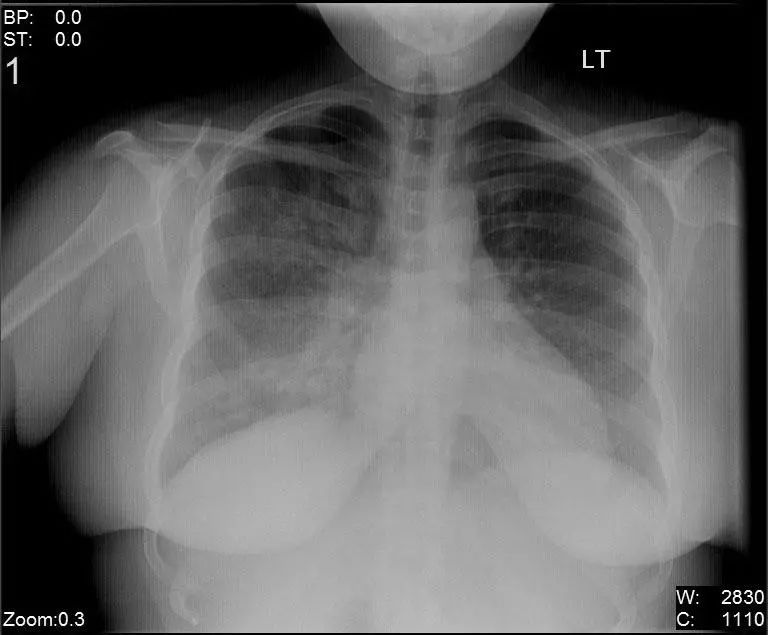

图2.3 31岁流感肺炎患者双肺间质浸润。

图2.4 2个月龄男孩肺炎患者,右中叶浸润,呼吸道合胞病毒(RSV)感染。